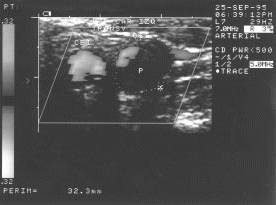

Figura 20.- Color Doppler Energy de la bifurcación carotidea, con estenosis severa en el bulbo.